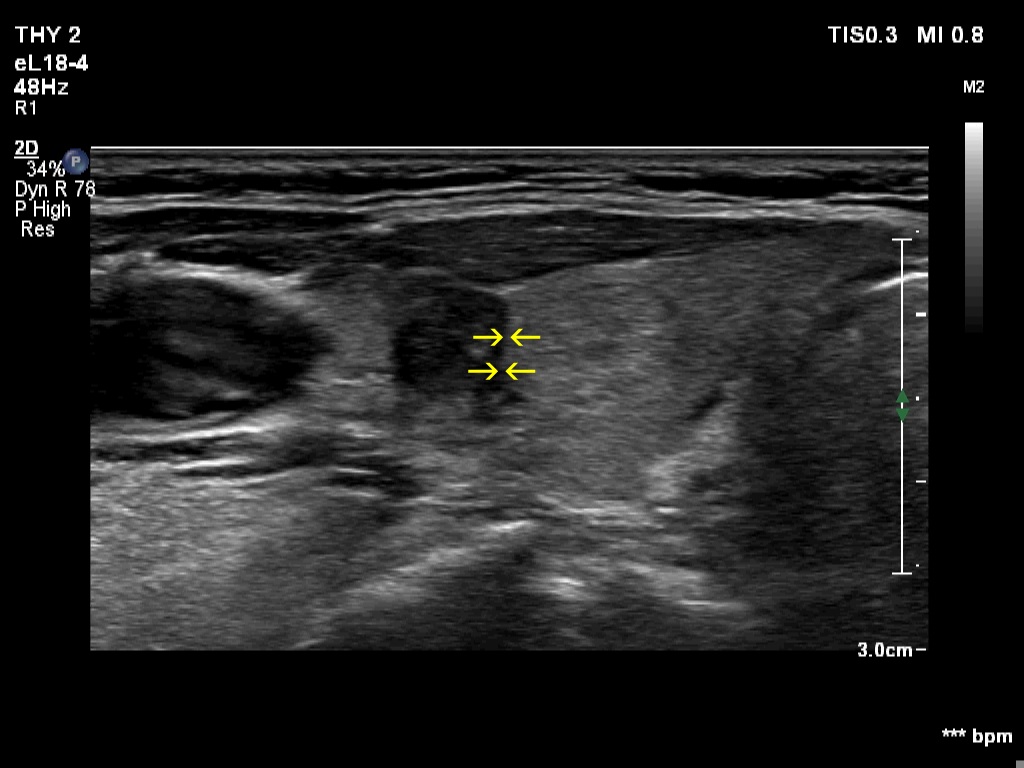

Halo sign and vascular pattern of nodules - case 2255 (ultrasonographic picture 6b)

Right lobe, transverse scan, enlargement. The yellow arrows point to the borders between the lateral hypoechoic and the medial echonormal nodule.